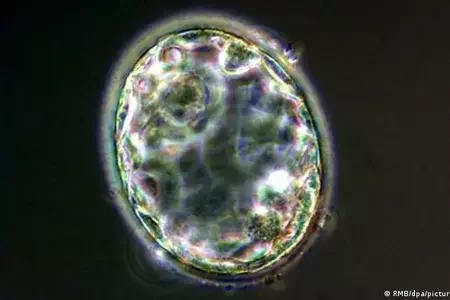

Ученые создали первую полноценную модель человеческого эмбриона